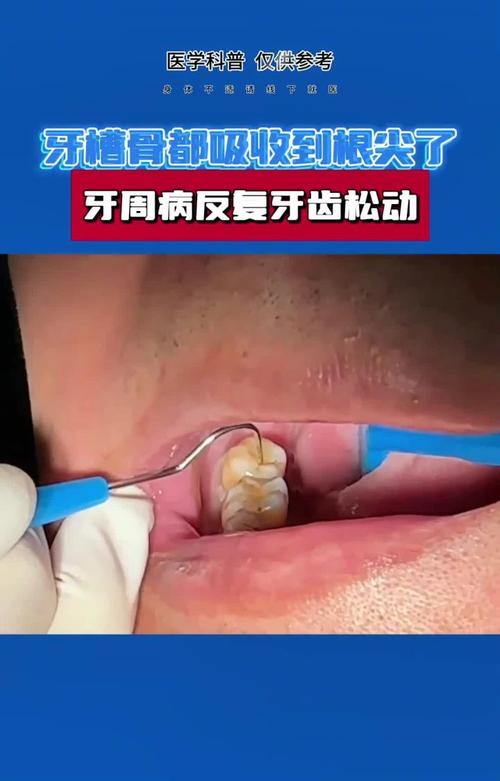

牙槽骨吸收严重确实给种植牙带来了挑战,但这并不意味着无法进行种植牙治疗,现代口腔种植学已经发展出多种技术来应对这种情况,以下是对严重牙槽骨吸收种植牙的详细分析和解决方案:

🧐 核心问题:骨量不足

种植牙成功的关键基础之一是足够的骨量来为种植体提供稳定的支撑,牙槽骨吸收后,高度、宽度和密度都可能不足,导致:

- 无法植入足够长度和直径的种植体: 种植体过短或过细,稳定性差,容易失败。

- 种植体位置不佳: 可能靠近重要解剖结构(如下颌神经管、上颌窦),增加手术风险。

- 缺乏软组织支撑: 骨量不足往往伴随牙龈萎缩,影响最终修复体的美观和功能。

- 长期稳定性风险: 即使勉强植入,骨量不足也可能导致种植体周围骨继续吸收,最终松动失败。

- 牙周健康是前提: 未控制的牙周病是种植失败的主要原因之一,必须先进行系统、彻底的牙周治疗并长期维护。